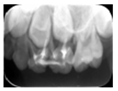

65MO深大龋洞,色棕黄,质软,叩痛(+),不松动,牙龈红肿,未见瘘管。 X线片示:冠部低密度影达髓腔,根分歧区大面积低密度影,近远中根内侧壁见吸收。25牙胚存,未拍全。 64MO深大龋洞,色棕黄,质软,叩痛(+),不松动,牙龈略红肿。 X线片示:根分歧区密度减低。 84OD深大龋洞,色棕黄,质软,叩痛(-),不松动, 85MO牙色充填体周围见龋坏,色黑,质软,叩痛(±),不松动,龈无异常。 X线片示:根周见低密度影,44,45牙胚存,未拍全。 54DOL深大龋洞,色黑,质软,叩痛(-),不松动, 55O窝沟色黑,卡探针,叩痛(-),不松动,龈无异常。 74OD,75MO半年前曾于外院行充填治疗,现检查见充填体边缘色黑,卡探针,充填体略有松动。

诊断:64,65,84,85慢性根尖周炎;54DOL深龋,55O中龋;74OD,75MO继发深龋 处置:64,65,84,85根管治疗 54DOL,55O行充填治疗 74OD,75MO去除旧充填体后充填治疗